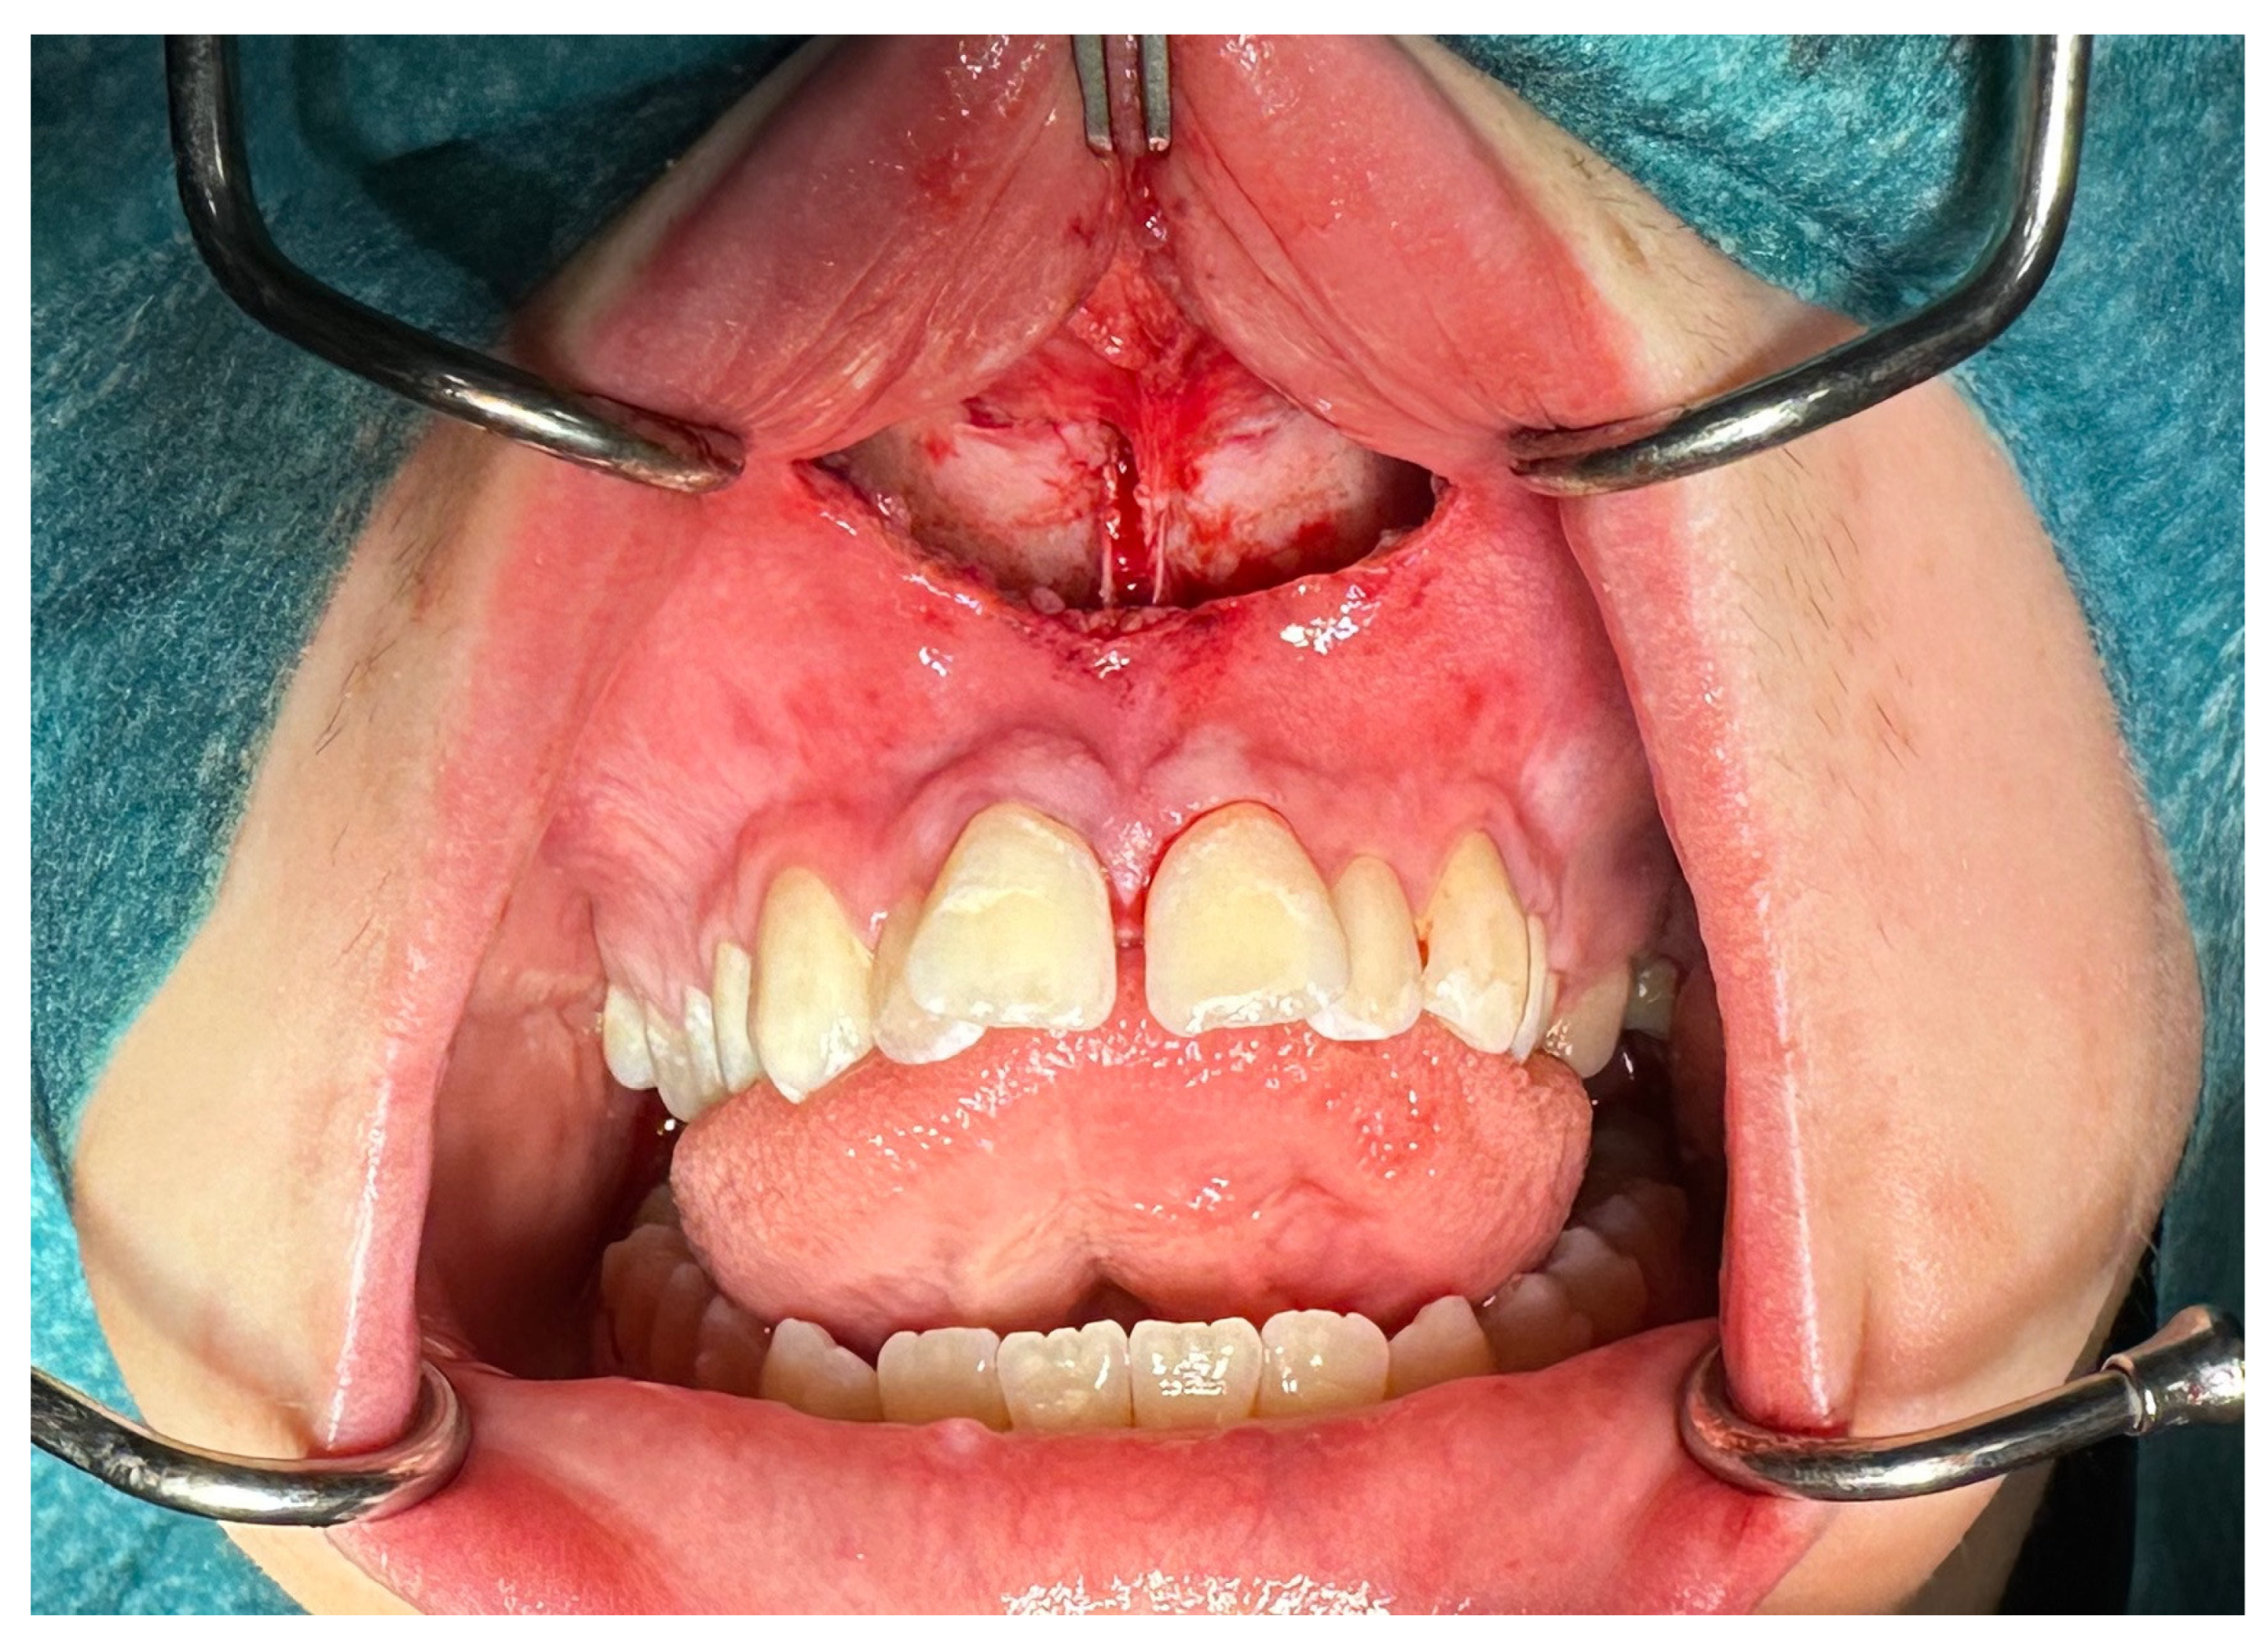

View attachment 4893948

View attachment 4893948